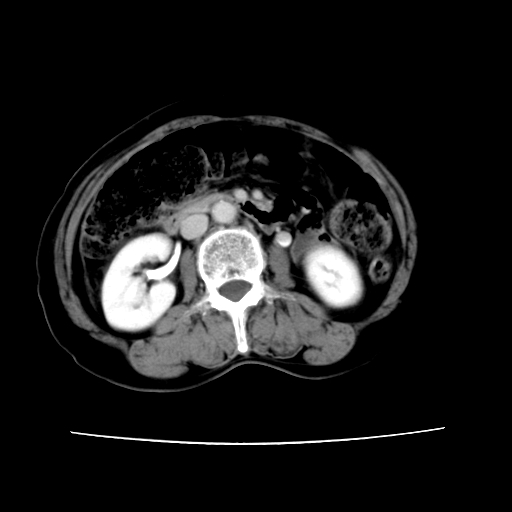

2008-11-10ct平扫(其间去中山医院诊治未行特殊治疗)

2008-11-10ct平扫见并肝内、血膜下血肿基本吸收,肝内低密度灶缩小。此时再做增强ct应有显着意义。对患者/医者都好!

从平扫+增强及治疗后复查片,病变明显缩小,不考虑肝癌出血可能,还是考虑为良性病变可能性大;单纯血肿并包膜下积液吧,病变强化没法解释,肝血管破裂出血吧,增强不符合典型血管瘤的表现,良性肿瘤破裂出血吧,复查片看来好像也不太支持(没做强化也不太好说)。本人还是考虑单纯肝内血肿并包膜下积液,强化是不是血管有外渗。

患者自6月至11月,如果是肝癌,没有经过特殊治疗,想必应该会有所进展吧,而不是ct所见,反而似有病灶减小的趋势。建议增强。

同意肝内肿块破裂致腹部疼痛,但不考虑肿瘤及血管瘤,增强不是血管瘤的特点,肿瘤半年时间内未经特殊治疗竟然快消失?考虑炎性改变或脓肿或寄生虫

病变破裂出血应首先考虑,病变性质即可能是恶性也可能是良性,楼主说患者到上级医院检查未见癌细胞,以良性可能性大,首先考虑腺瘤破裂出血可能。

追问病史,患者有过度用力病史,当时立即感腹痛;所以还考虑肝破裂可能性大。